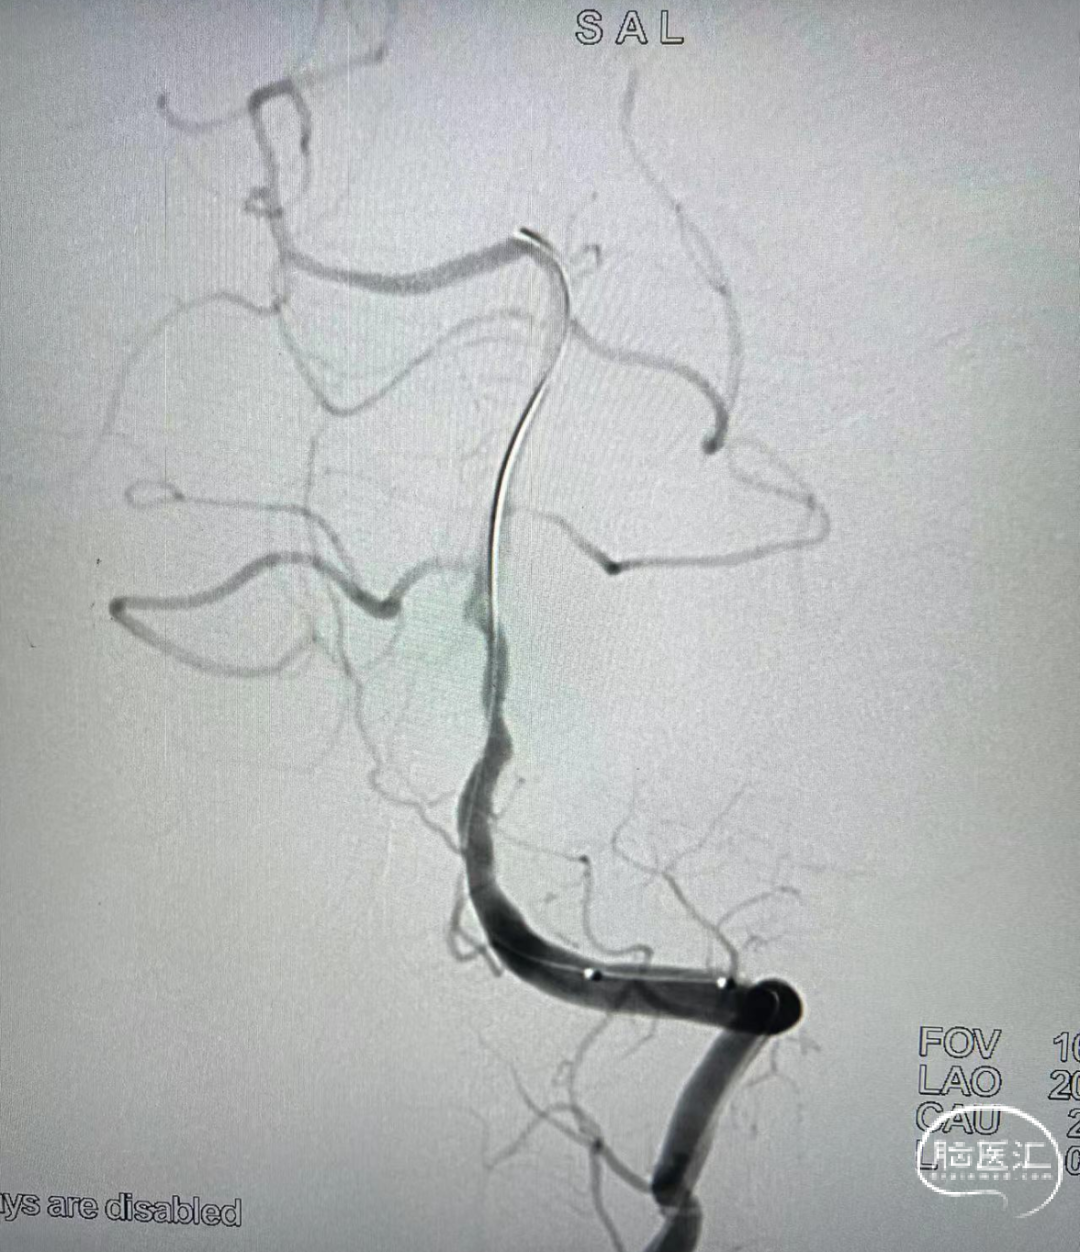

支架释放后,即刻造影,可见血管狭窄明显改善。

释放支架后左侧椎动脉正位造影,狭窄明显改善,支架释放后远端血流无影响。